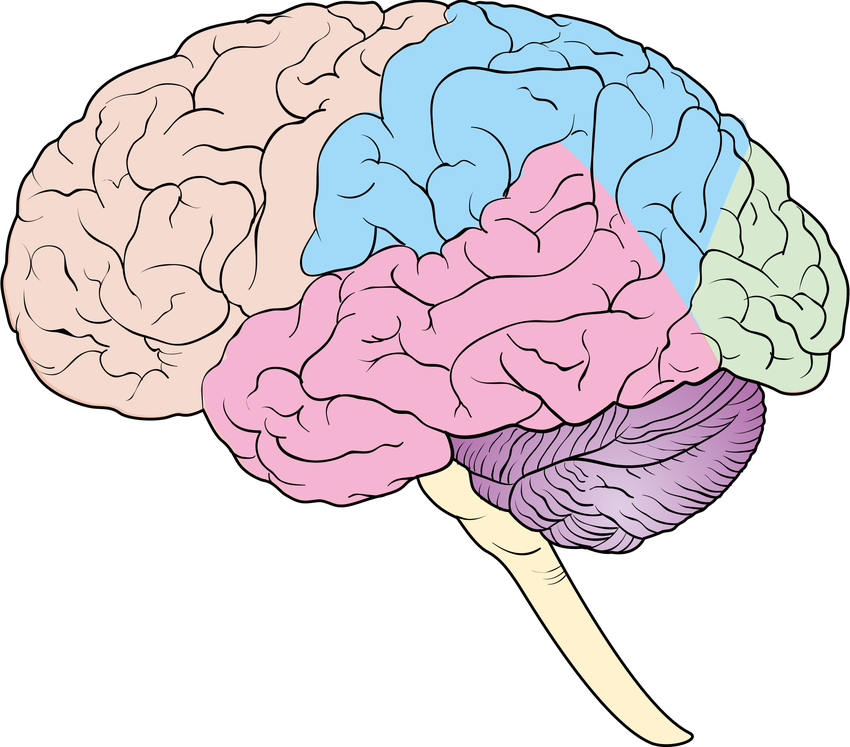

Строение отделов головного мозга задний мозг

Мозг доли